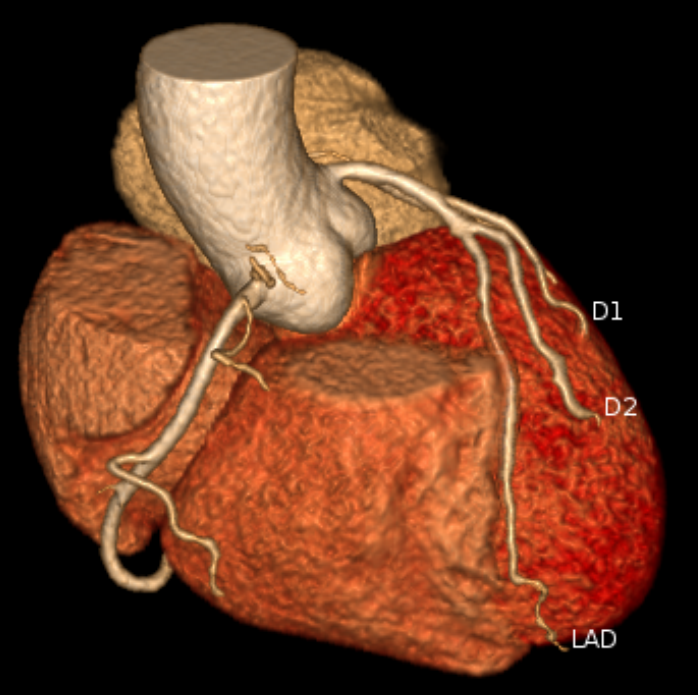

注射少量碘造影剂后,通过CT扫描,计算机能把心脏血管的走行、分支、狭窄处重建出一张高清的3D立体图像。

(1)无创诊断冠心病“金标准”:对冠状动脉显著狭窄(≥50%)的诊断敏感度、特异度均超90%,阴性预测值接近99%——检查结果正常,基本可排除冠心病,避免不必要的有创造影,减少患者痛苦与风险;

(2)揪出“隐形杀手”易损斑块:不仅能判断血管狭窄程度,更能精准识别钙化斑块、非钙化斑块(软斑块)、混合斑块,尤其是易损斑块。这类斑块看似稳定,却可能突然破裂引发急性心梗,是猝死的核心隐患,而传统检查难以发现,CTA能提前3-5年锁定风险;

(3)术后随访“好帮手”:可评估冠脉支架术后通畅性、搭桥术后血管桥形态,为术后干预方案调整提供精准依据。